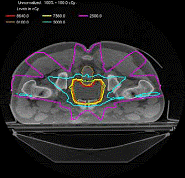

图象引导放射治疗设备(Image Guide RadioTherapy-IGRT)